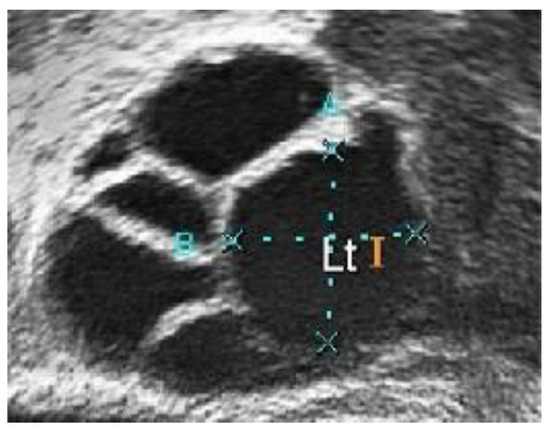

Figure 5.

Ultrasound image with high intensity of light pixels.